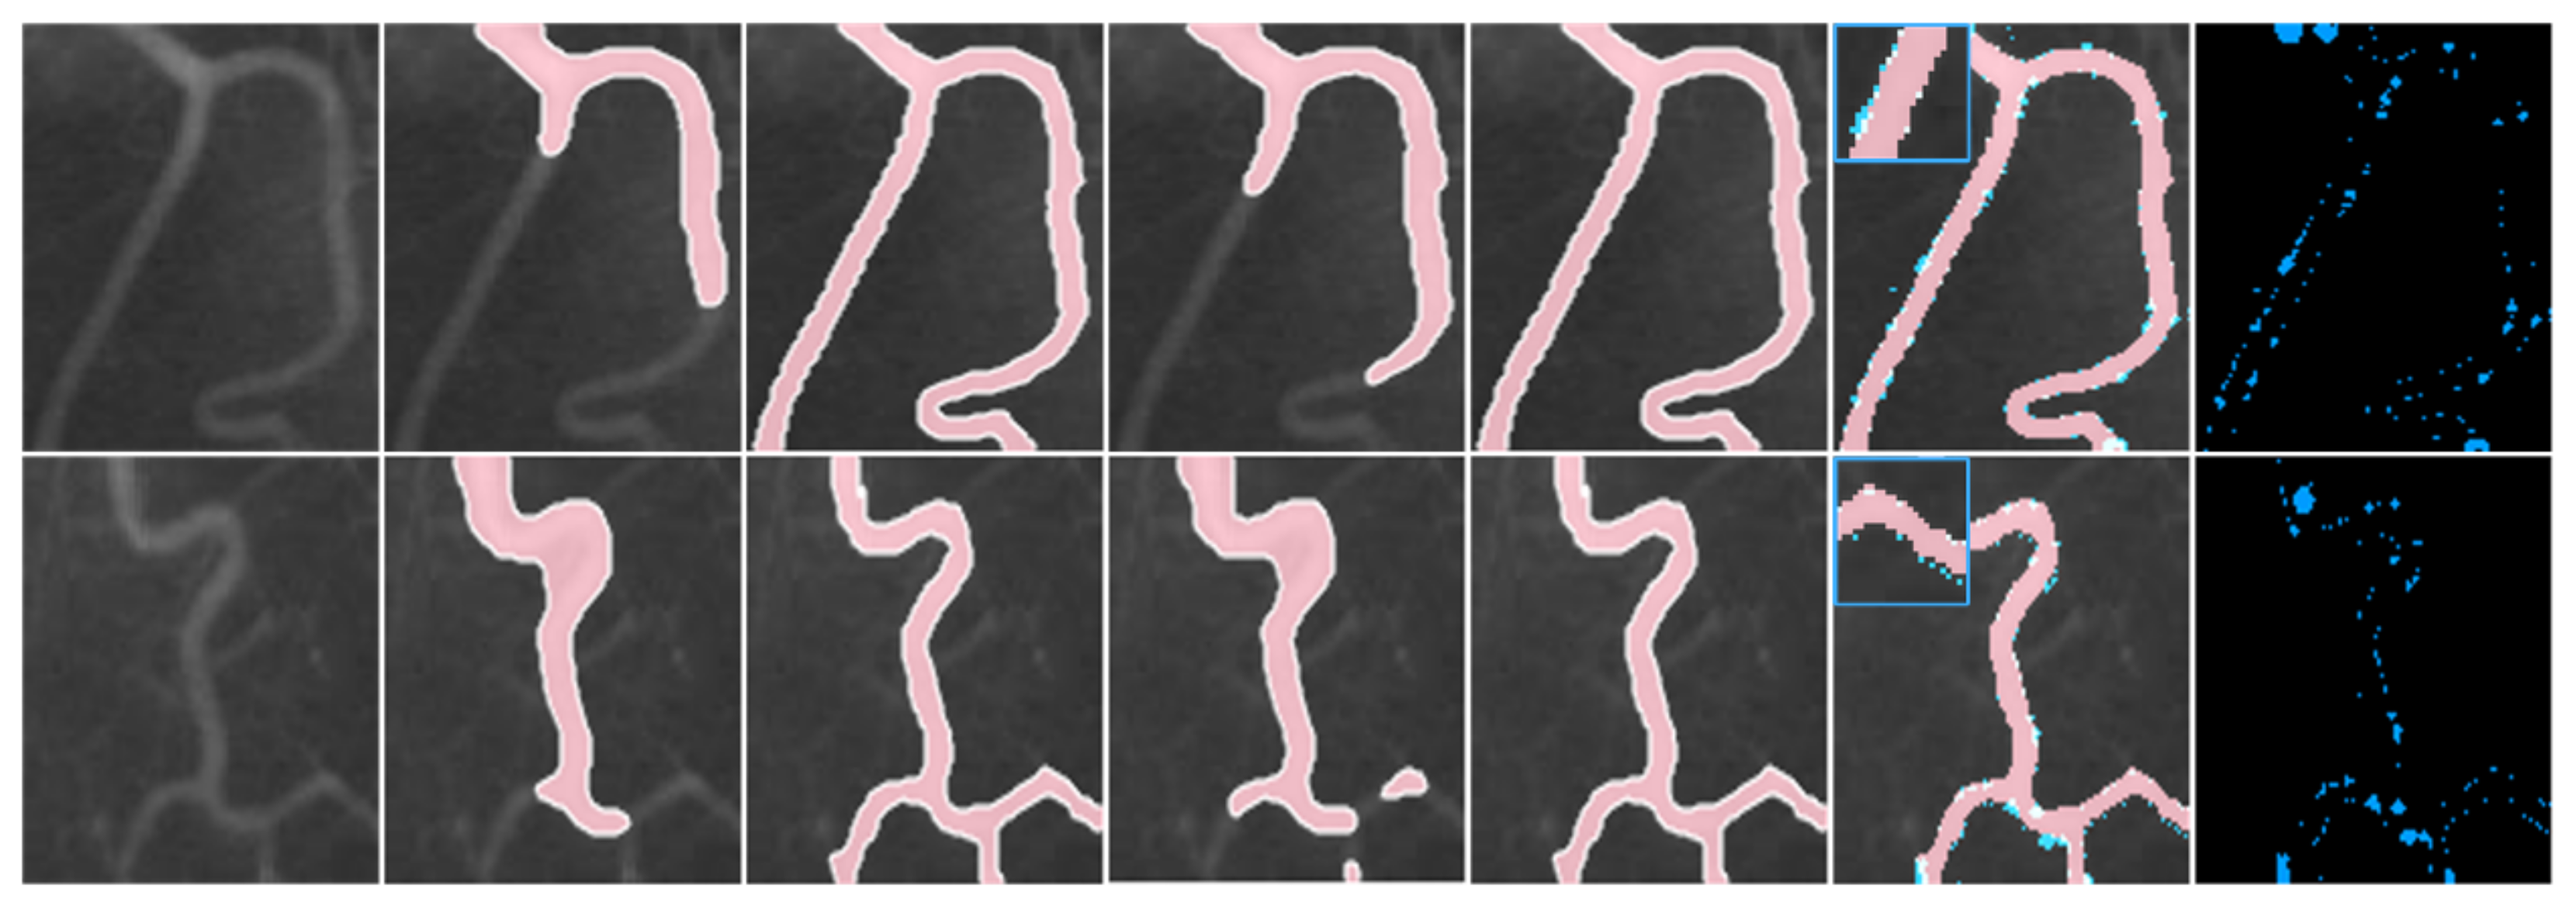

4.1. The Qualitative Experiments